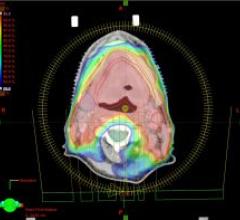

September 15, 2008 - Varian Medical Systems is demonstrating its full range of technologies and products aimed at ...

September 15, 2008 - CMS Inc., an Elekta company, today commercially launched its new 4D treatment planning solution ...

September 12, 2008 – Elekta said today its ERGO 1.7.1. for Volumetric Modulated Arc Therapy (VMAT) is now available ...